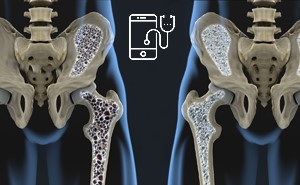

Osteoporosis is characterized by

reduced bone mass and fragmentation of bone architecture, resulting in an

increased risk of fracture. Approximately 1 in 2 women and 1 in 5 men aged 50

years or older will experience an osteoporotic fracture in their remaining lifetime.

Osteoporosis is a bone disorder

that increases a person’s risk of fracture due to low bone mineral density

(BMD), impaired bone microarchitecture/mineralization, and/or decreased bone

strength. Osteoporotic fractures most commonly occur at the hip, spine and

wrist.

Overview of OsteoporosisOsteoporosis is a disease

characterized by low bone mass and deterioration of bone tissue and bone

structure, which can lead to increased bone fragility and risk of fracture. The most common fractures associated

with osteoporosis are in the hip, spine, wrist, and shoulder.

Osteoporosis is the major cause